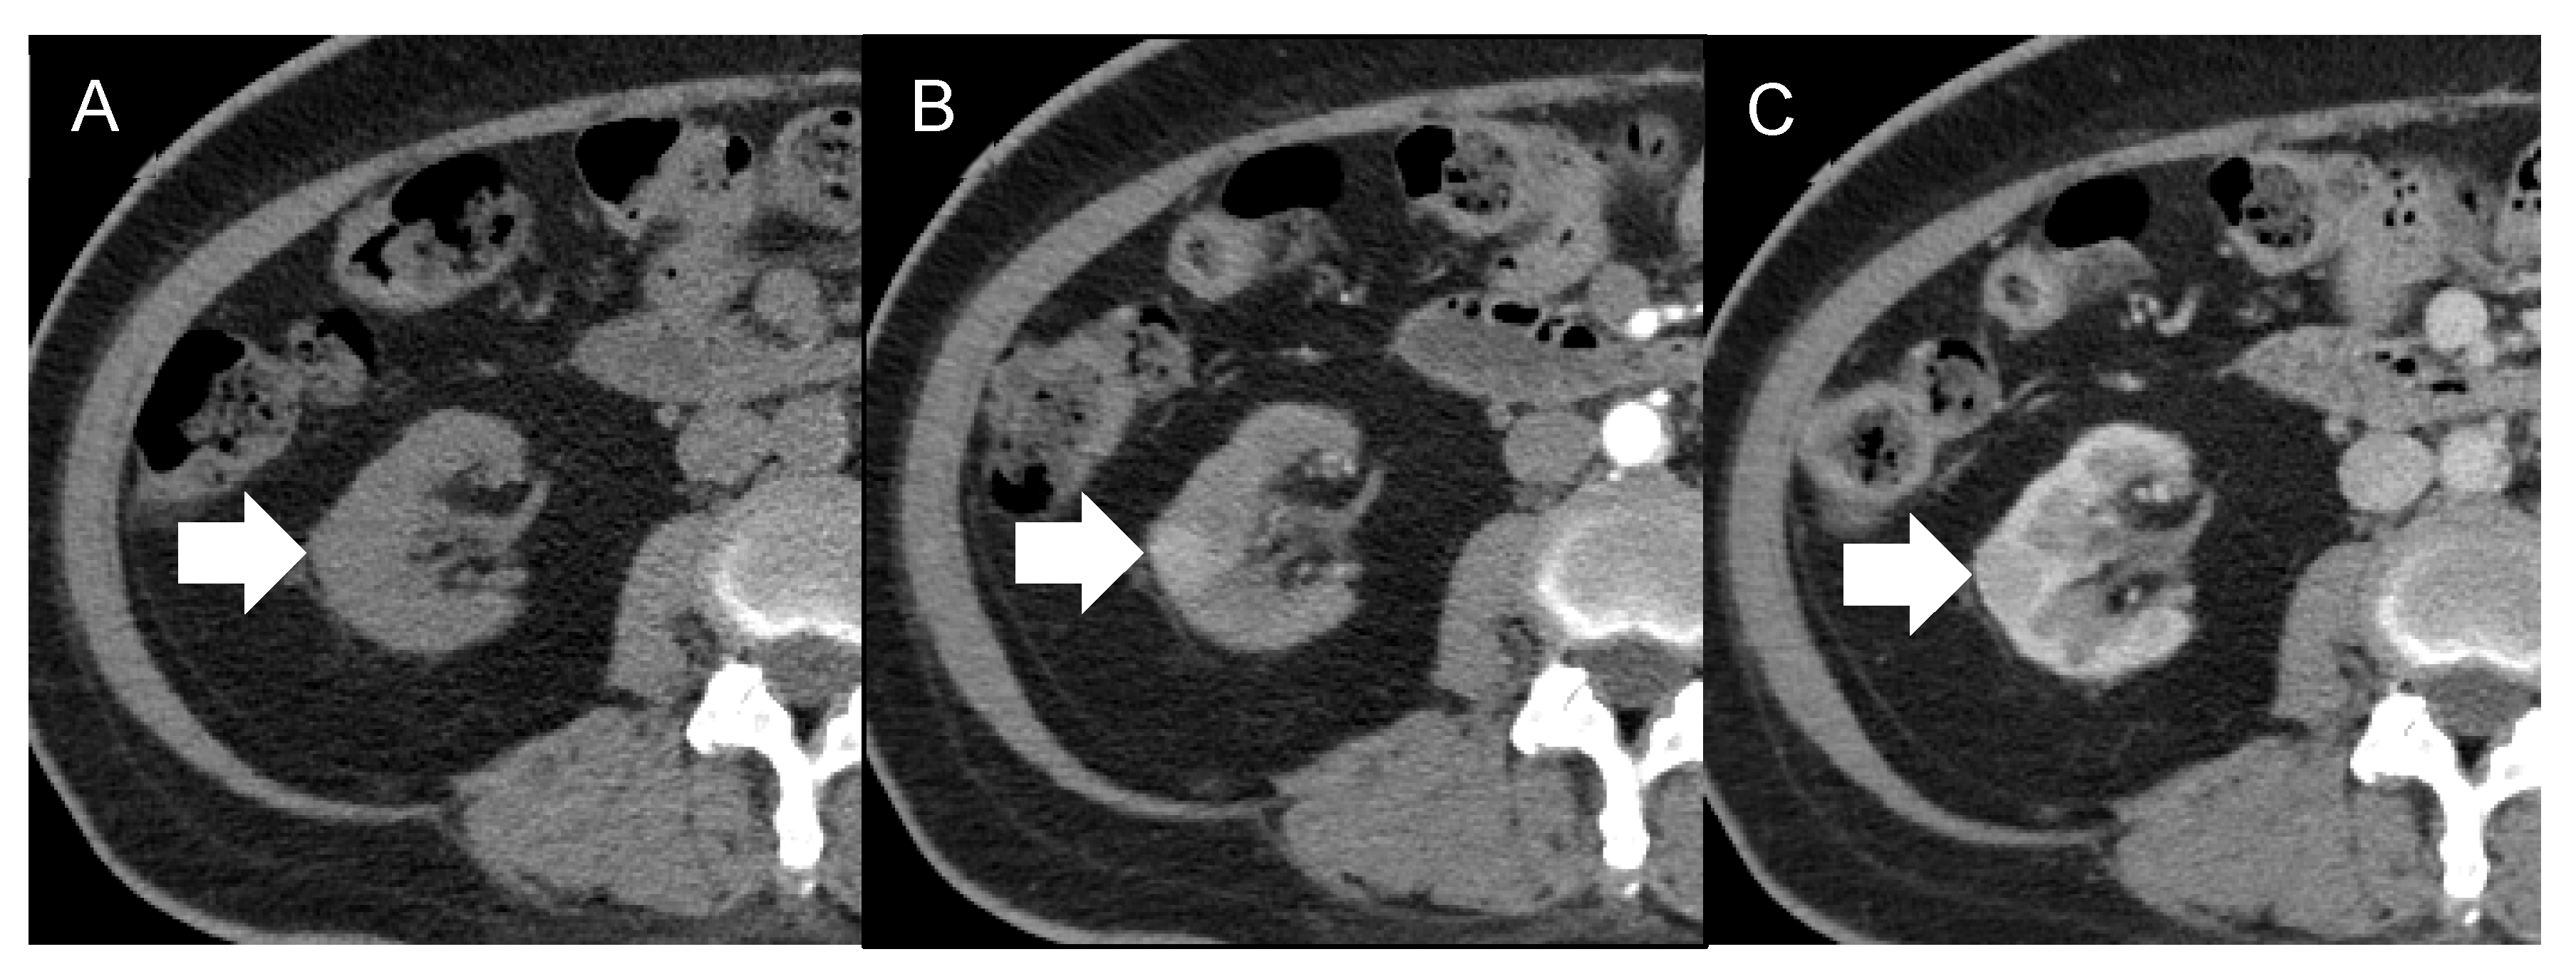

| 8 | 56/F | None Incidentally found | ESRD, HTN, diabetes, hyperlipidemia | Right lateroposterior cortex of the lower pole | 1.3 cm | US: Lesion detected MRI: Iso-intensity in the T1- and T2-weighted images and low ADC value CT: Early enhancement, suspecting RCC | HV | Laparoscopic nephroureterectomy | Free of disease 17 months after surgery | Our case |